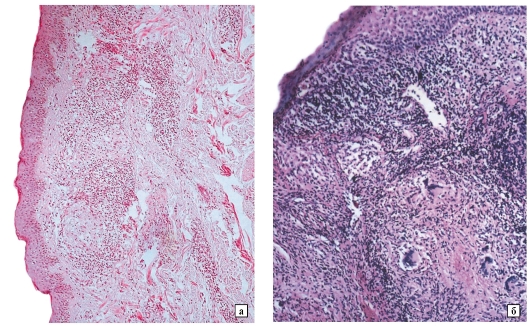

Микроскопический взгляд на мишитарный туберкулез легкого: фотодокументация

Раздел: Снимки-откровения